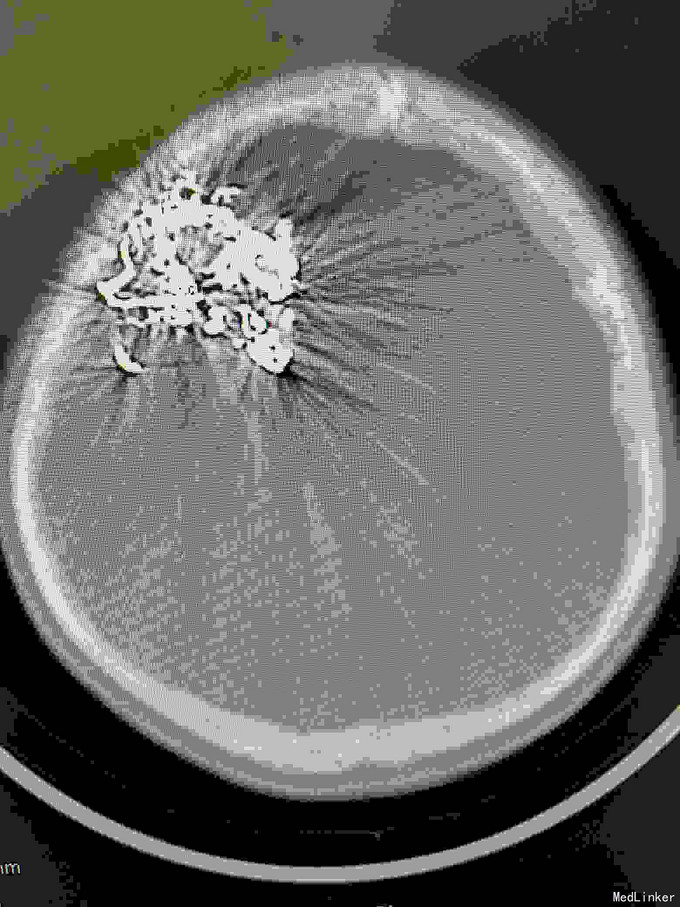

右额AVM

男,23岁。右额AVM。分次治疗。